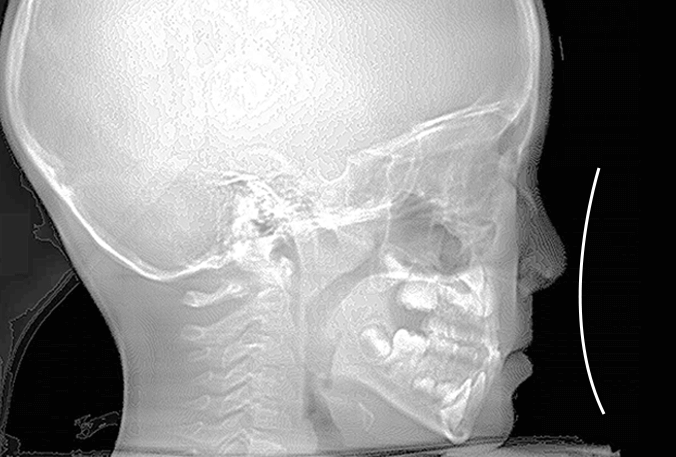

出っ歯を目立たずしっかり治したい。とのご希望、ビジネスシーンでも目立たないインビザラインを選択なさいました。30代男性の症例です。

治療計画は

抜歯した上顎も親知らずまできれいに並べたことで、上下ともに14本ずつ=非抜歯と同じ28本の歯列が完成しました。

治療から2年後も+ホワイトニングできれいな歯並びを保っています。

出っ歯が気になる

上顎前突、過蓋咬合

30代男性

3.5年

36回

唇側矯正、圧下用インプラントアンカー

矯正:1,270,500円+毎月調整量:6,050円

上顎2本抜歯して前歯を下げます。

奥歯のかみ合わせを治します。

インプラントアンカーを使用して前歯をしっかりコントロール、

過蓋咬合(かみ合わせの深さ)を改善しました。